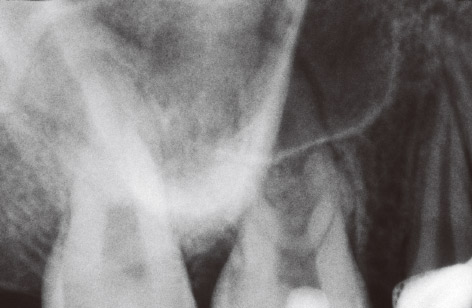

図1 上顎右側第一大臼歯のデンタルX線写真。口蓋根に歯根膜腔の拡大が認められた。頰側2根の病変は明らかではない。歯髄保存処置後4年、矯正開始後2年8ヵ月。咬合調整により痛みは消失した。

図2A 矯正用インプラントアンカー埋入のため撮像した(管電流3mA)。軽度の打診痛以外の症状はなかった。矢状断(頰側根):頰側2根に病変が認められる。根尖病変により上顎洞底の骨が破壊されている。